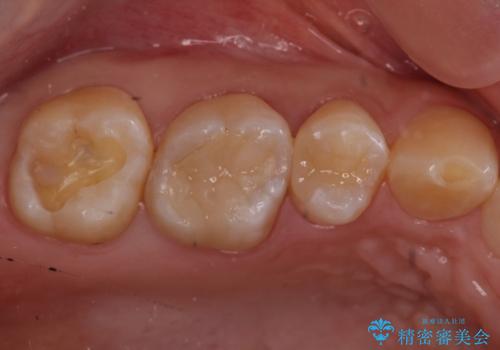

銀歯を白くしたい

- 奥歯の銀の詰め物を白くしたいとのことで来院されました。

- 右上7 セラミックインレー 77,000円費用は治療当時の料金となります

今回は大きな虫歯もなかったため、1回当たり30分程度の治療時間で計2回の来院回数で治療を終えることができました。